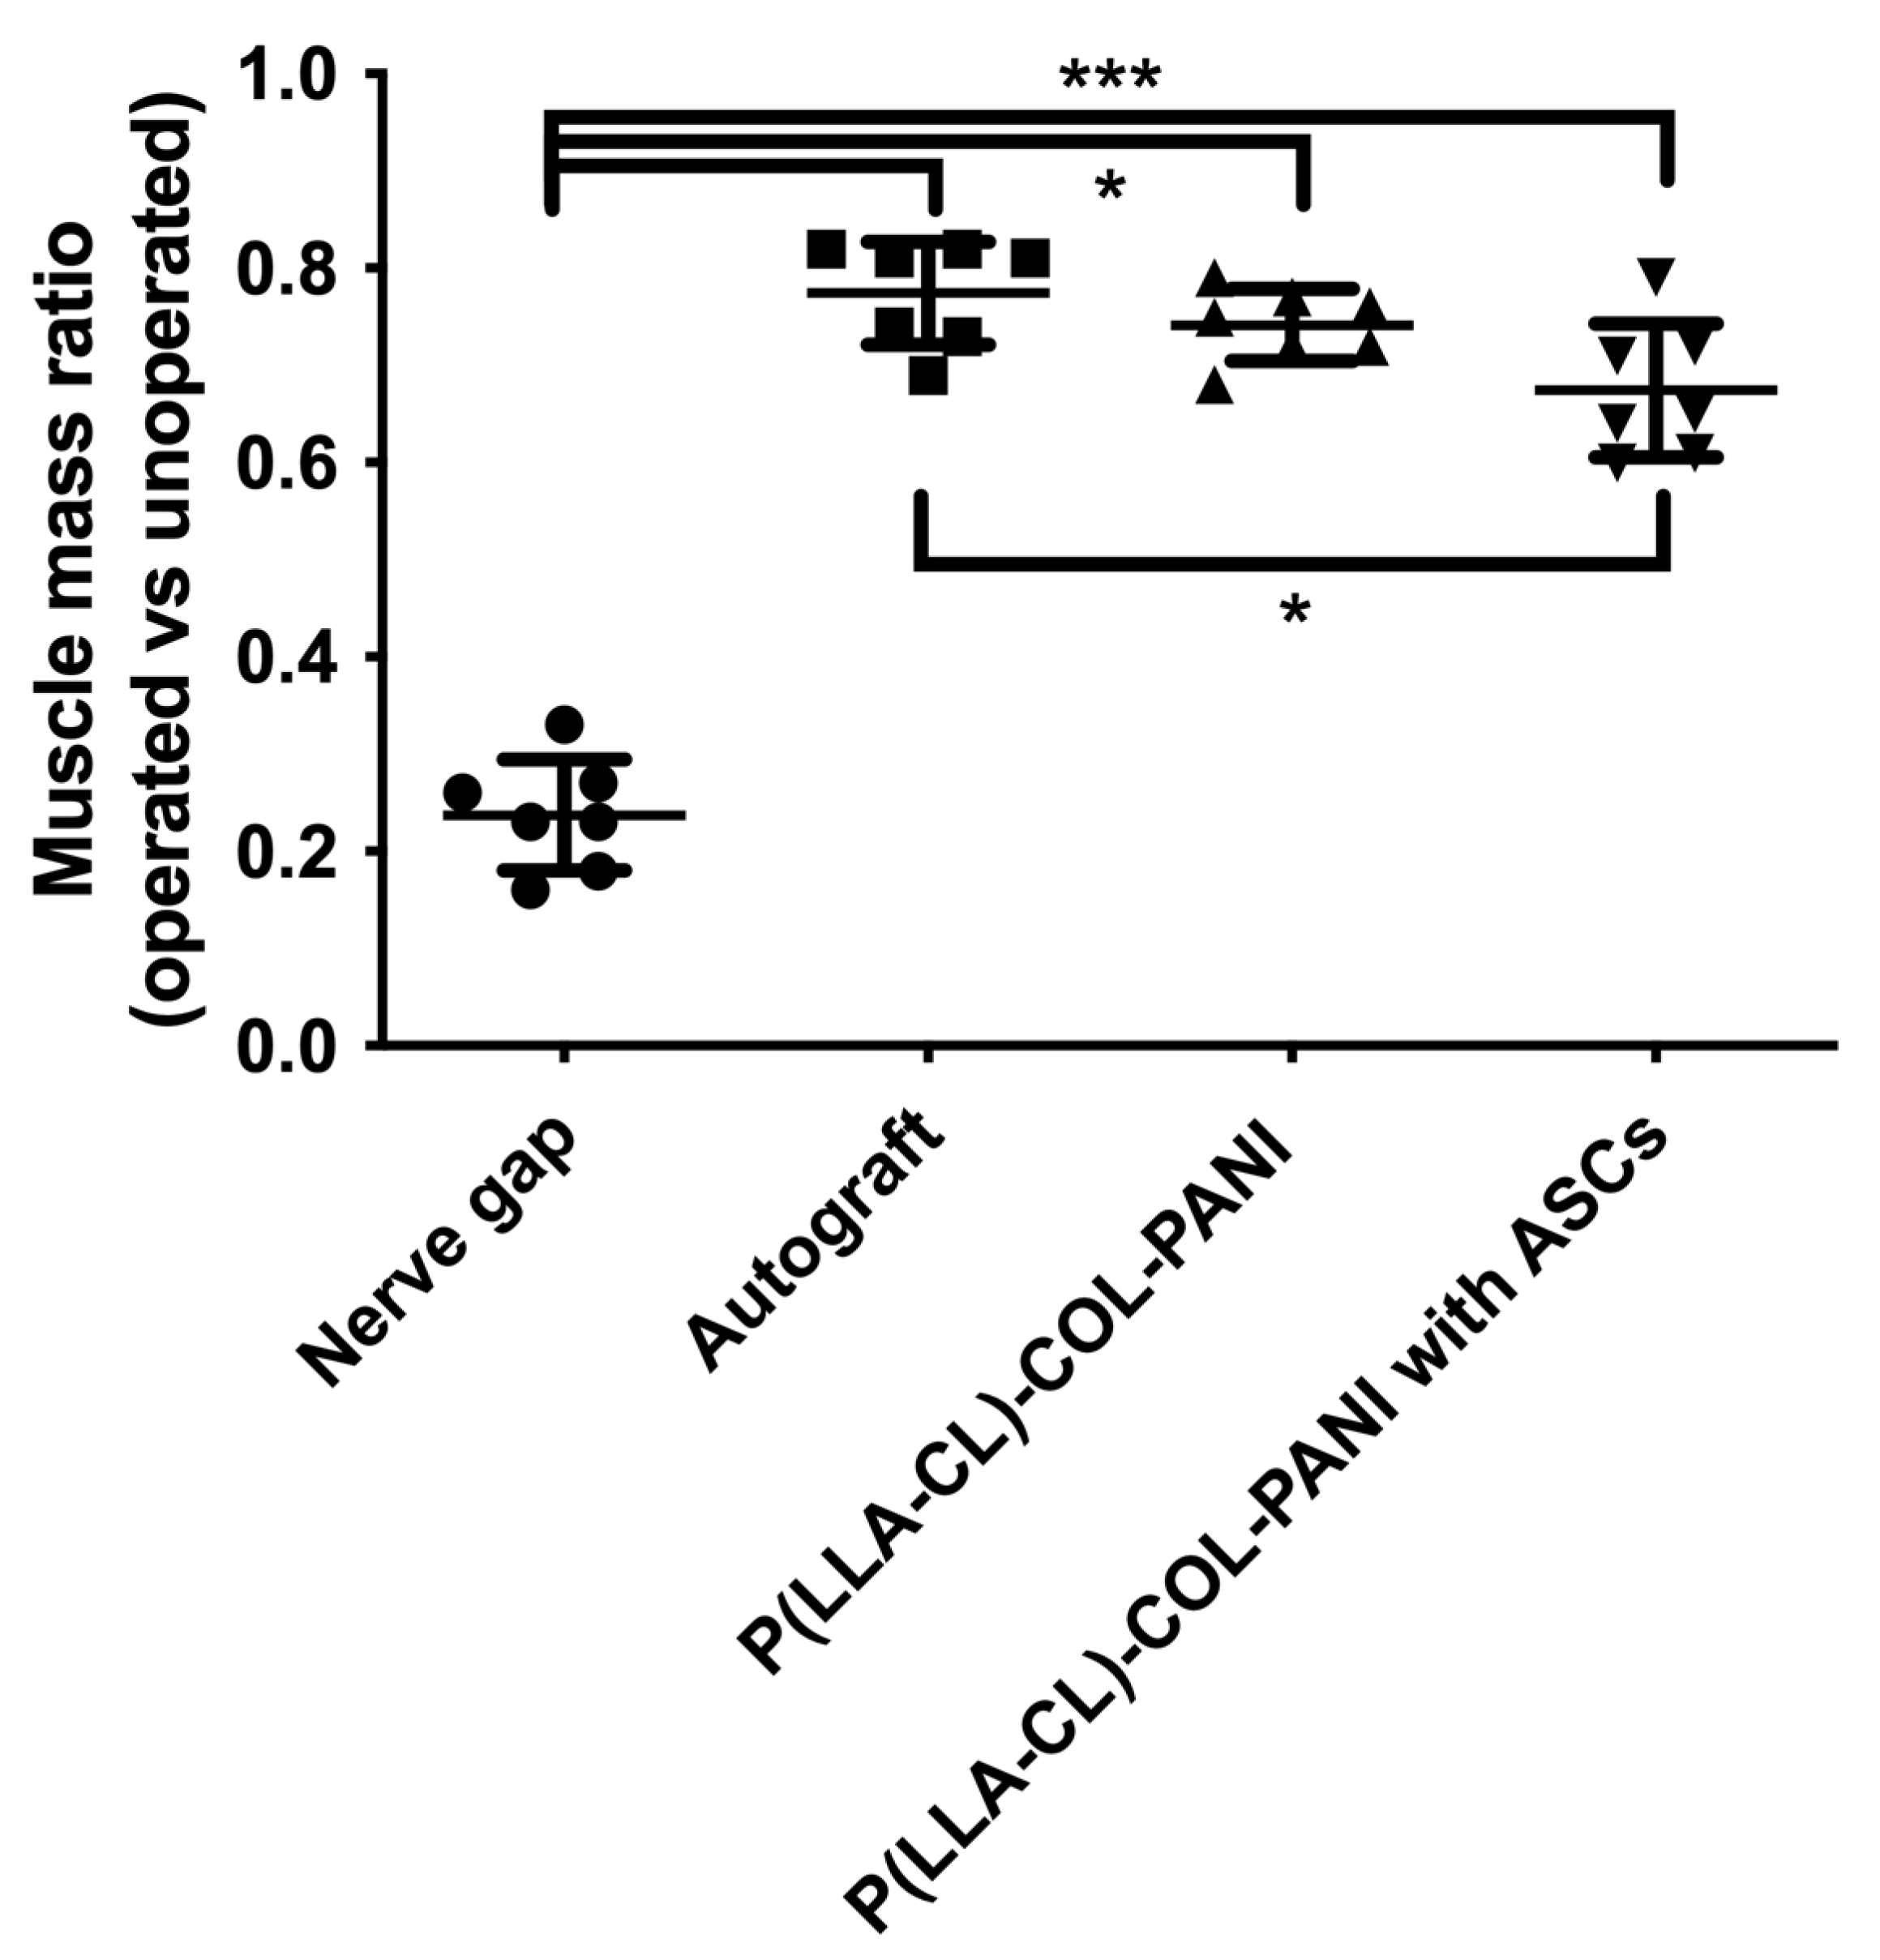

2.4. Muscular Tissue